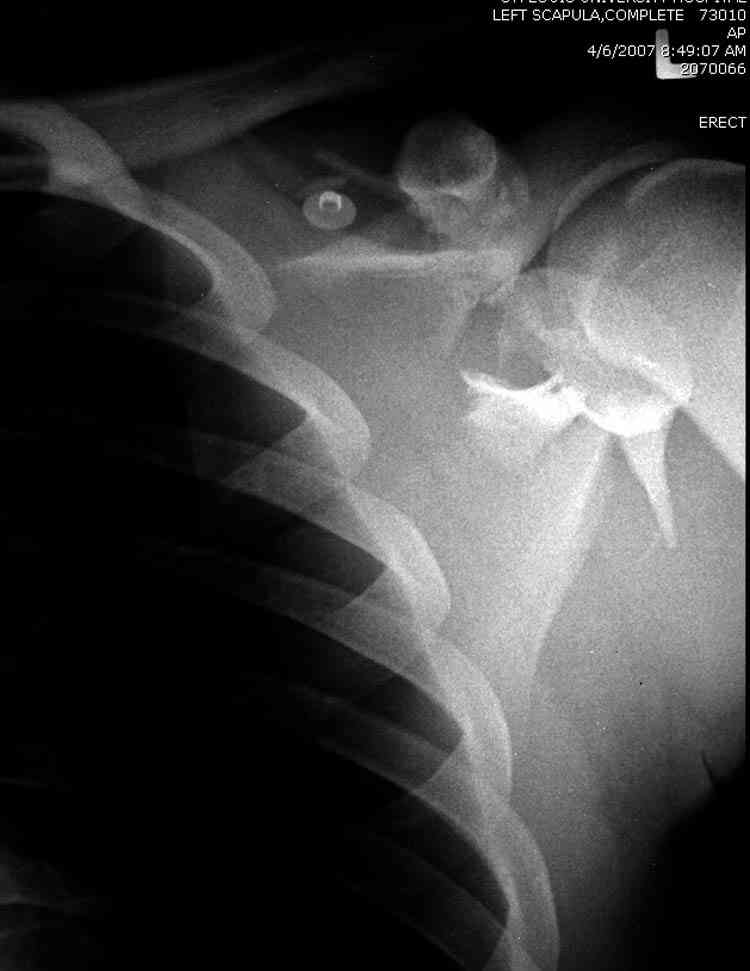

дравствуйте, коллеги. Мужчина 24 лет. Сегодня был прооперирован по Сушко-Илизарову (давно порывался, наконец-то руки дошли :)) На снимке перелом угла лопатки. Довольно крупный размер осколка. Следует ли оперировать такой перелом?Если есть резон оперативного лечения, то каким образом? (рекон. пластина, закрыто пришпилить спицами, винтами). ЭОПа в наличии нет. В области лопатки массивный отек мягких тканей. С уважением, Заднепровский Никита Николаевич

А где там сломанный угол лопатки? Стрелочкой покажите pls?

Посмотрел пациента под рентгеноскопом, определяется изолированный перелом верхнего медиального угла лопатки. Вопрос об операции отпал. Больной машет крылом как пропеллером, пришлось ограничить активность дисциплинирующей "косынкой" ... :))) Отек мягких тканей в области